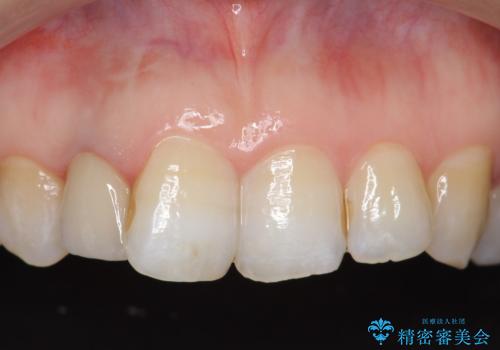

オールセラミッククラウン 変色が気になる前歯の治療

- 右上2番目の歯の変色が気になるといらっしゃった方の症例です。

再根管治療終了後、オールセラミッククラウンによる補綴を行いました。

今回用いたオールセラミッククラウンはジルコニアフレームという白い素材の上にセラミックを盛っているため、審美性が非常に高いのが特徴です。